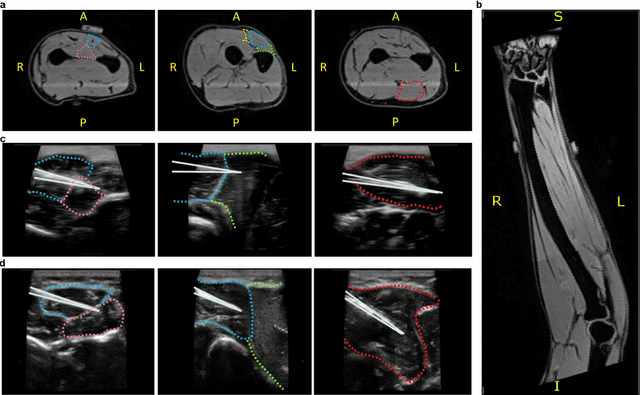

Abstract:Decoding nervous system activity is a key challenge in neuroscience and neural interfacing. In this study, we propose a novel neural decoding system that enables unprecedented large-scale sampling of muscle activity. Using micro-electrode arrays with more than 100 channels embedded within the forearm muscles, we recorded high-density signals that captured multi-unit motor neuron activity. This extensive sampling was complemented by advanced methods for neural decomposition, analysis, and classification, allowing us to accurately detect and interpret the spiking activity of spinal motor neurons that innervate hand muscles. We evaluated this system in two healthy participants, each implanted with three electromyogram (EMG) micro-electrode arrays (comprising 40 electrodes each) in the forearm. These arrays recorded muscle activity during both single- and multi-digit isometric contractions. For the first time under controlled conditions, we demonstrate that multi-digit tasks elicit unique patterns of motor neuron recruitment specific to each task, rather than employing combinations of recruitment patterns from single-digit tasks. This observation led us to hypothesize that hand tasks could be classified with high precision based on the decoded neural activity. We achieved perfect classification accuracy (100%) across 12 distinct single- and multi-digit tasks, and consistently high accuracy (>96\%) across all conditions and subjects, for up to 16 task classes. These results significantly outperformed conventional EMG classification methods. The exceptional performance of this system paves the way for developing advanced neural interfaces based on invasive high-density EMG technology. This innovation could greatly enhance human-computer interaction and lead to substantial improvements in assistive technologies, offering new possibilities for restoring motor function in clinical applications.